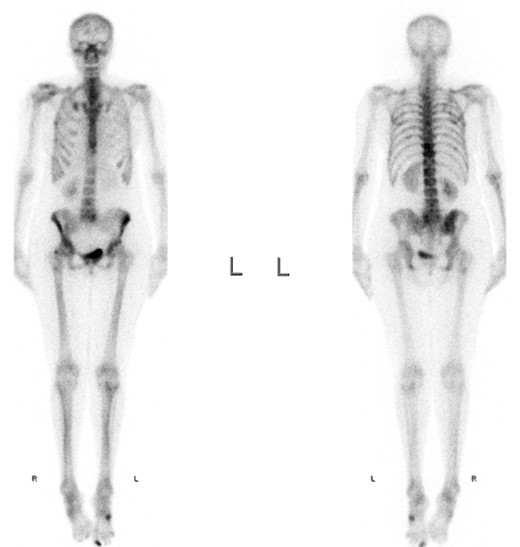

A full-body skeletal scintigraphy was done, which did not show an obvious pathology in the right TMJ (Fig. 3). Due to this, a SPECT/CT was performed for clarification. High uptake of nuclides was seen around the osteolysis of the right condyle (Fig. 4). Sclerotic changes without increased uptake were noted in the left condyle (Fig. 5).

The sclerosis of the left TMJ was suspected to be a non-active metastasis.

In summary, from the radiological findings bilateral TMJ metastases were diagnosed, which were, however, not confirmed histologically.